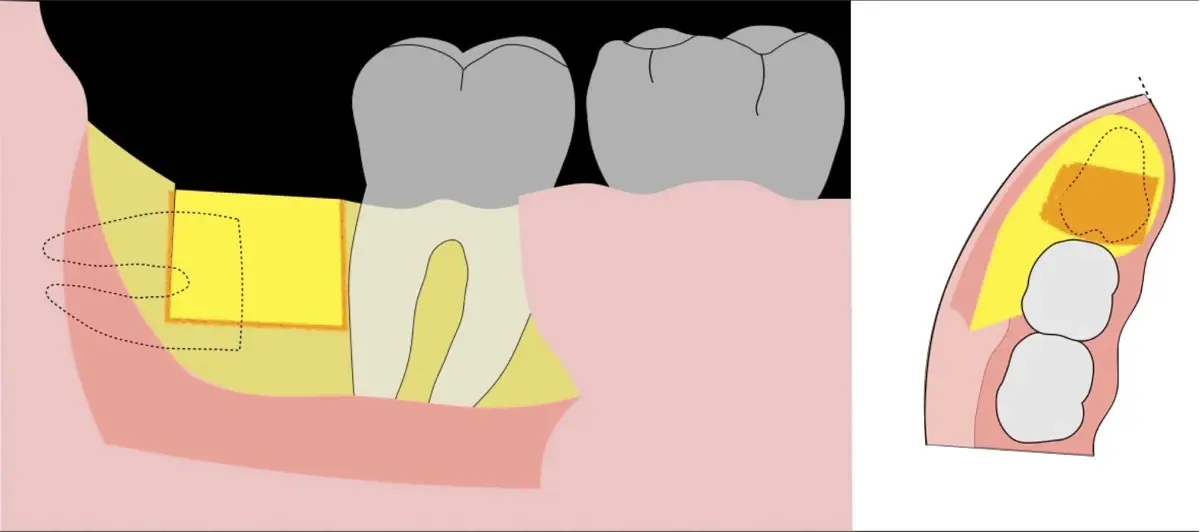

Figura 7. Eliminación del fragmento vestibular.